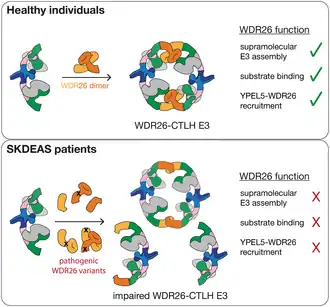

The WDR26 gene provides instructions for making the WD repeat-containing protein 26 (WDR26), which is produced by most human cells.[2] One of WDR26's many roles is to help build a larger structure called the C-terminal to LisH E3 ubiquitin ligase complex (CTLH E3 complex), which marks several proteins for degradation. It also helps anchor another component, Yippee-Like 5, to support the stability and function of this complex. As a part of its role, WDR26 directs the degradation of specific proteins, such as HMG-box transcription factor 1, a transcriptional repressor involved in gene regulation.[9]

WDR26 also helps stabilize a protein called Ran-binding protein 9 (RANBP9; green components in the image). RANBP9 brings the CTLH complex to DNA regions (chromatin), where it helps control gene expression by affecting how accessible certain genes are to transcription factors like Nuclear factor I and AP-1.[10] Skraban–Deardorff syndrome is caused by pathogenic variants of the WDR26 gene. These variants can occur due to missense, nonsense or frameshift variations.[7] These variants reduce the amount of functional WDR26 protein, disrupting protein degradation, gene regulation and expression—processes important during the development of the nervous system.[9][10]

A single abnormal copy of the WDR26 gene is sufficient to cause Skraban–Deardorff syndrome, as the remaining normal copy does not produce enough protein for proper function—a mechanism known as haploinsufficiency. Reported cases in the medical literature have been de novo, meaning the variants arose spontaneously and were not inherited from either parent. Because only one abnormal copy is needed to cause disease, the syndrome follows an autosomal dominant inheritance pattern, and an affected individual has a 50% chance of passing it on to each offspring.[7]